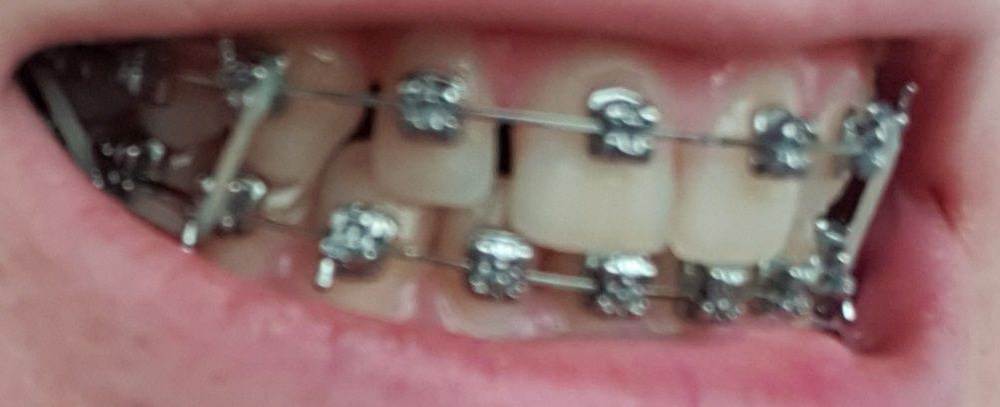

НадеждаВ Опубликовано 3 августа, 2022 Поделиться Опубликовано 3 августа, 2022 (изменено) Добрый день. Имеются 2 шипообразных резца. В стоматологии, где прохожу ортодонтическое лечение убеждают, что просто нарастить только их винирами не выйдет, т.к очень большие расстояния и если закрыть их, то боковые резцы по ширине будут неестественно широкими по отношению к центральным. Уменьшить промежутки тоже не видят возможности, т.к. сейчас передние зубы находятся между двумя нижними, при движении будут друг над другом. Поэтому предлагают установить 6 виниров от клыка до клыка, чтобы закрыть все промежутки и соблюсти соотношение ширины зубов. Действительно ли в моем случае это необходимо и нет реальной возможности ограничиться только двумя реставрациями с сохранением эстетики? Страшно пилить здоровые достаточно эстетичные зубы, особенно центральные резцы. На фото так же макет пластиковый, как мне предлагают сделать. Действительно ли боковые резцы должны быть несколько наклонены к центральным, а не быть абсолютно прямыми и зениты могут быть не четко по центру от зуба, а несколько в сторону уходить? 2. Вопрос касаемо самих виниров. Я хотела бы отбелить свои зубы на сколько получится и чтобы виниры были неотличимы от родных зубов. Я читала, что емах выглядят серовато, подходит ли в моем случае этот способ или лучше виниры, которые делают на рефракторе? Они, как я поняла, выглядят естественнее и тоньше, поэтому и обточки требуют меньше. ( один из Резцов на столько мал, что на него вроде только коронку можно установить). 3. Как оценить опытность врача? У ортопеда опыт всего 4 года, вдруг спилит слишком много. Так же смущает их техник, т.к у него скорее всего тоже небольшой опыт, сможет ли он сделать действительно эстетичную реставрацию? Когда делали макет и меня спрашивали про форму, я сказала, чтобы она максимально была похожа на мою и на макете боковые резцы сделали скошенные, как мои сейчас, но стёсанные, ведь это не эстетично и техник должен был это понимать. Изменено 3 августа, 2022 пользователем НадеждаВ Ссылка на комментарий

chervoncevdaniil Опубликовано 3 августа, 2022 Поделиться Опубликовано 3 августа, 2022 (изменено) Вам делали восковое моделирование и примерку для 6 винировв судя по фото,оплатите и закажите воскове моделироввание с примеркой только на 2 винира и оцените результат. Если вас устроит,то почему делайте,если нет,то обсуждайте другие ваарианты с большим количеством зубов. Исходя из фото номер 2 с моделировкой,все выглядит очень гармонично в случае 6 виниров Изменено 3 августа, 2022 пользователем chervoncevdaniil 1 Ссылка на комментарий

НадеждаВ Опубликовано 4 августа, 2022 Автор Поделиться Опубликовано 4 августа, 2022 @chervoncevdaniil спасибо. Да, макет на 6 зубов. Согласна, что выглядит органично, но я переживаю за зубы, ведь они здоровые, нормальные, а если раз их спилить, то все (это не касается боковых Резцов) я переживаю за целесообразность портить эмаль только ради двух миллиметров винира. По поводу макета на два зуба наверно хорошая идея, только когда мне ставили обратно брекеты, то положение зубов немного поменялось, щель между центральными зубами ушла почти ( хотя изначально у меня вообще ее не было), я правильно понимаю, что по идее, если хоть что-то сдвинулось, то по идее нужно вообще опять гипсовую модель переделывать? ещё сканировали челюсть на 3д, но почему-то этот снимок вообще не использовали. Ссылка на комментарий